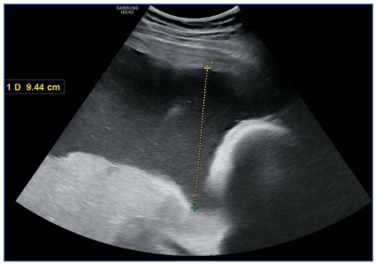

Fetal Double-Bubble Image: Is there Only Duodenal Atresia?

Marrakchi Salma, El Hassouni Fatima, Laasri Khadija, Allali Nazik, Chat Latifa and El Haddad Siham. 13(10): 01-05.